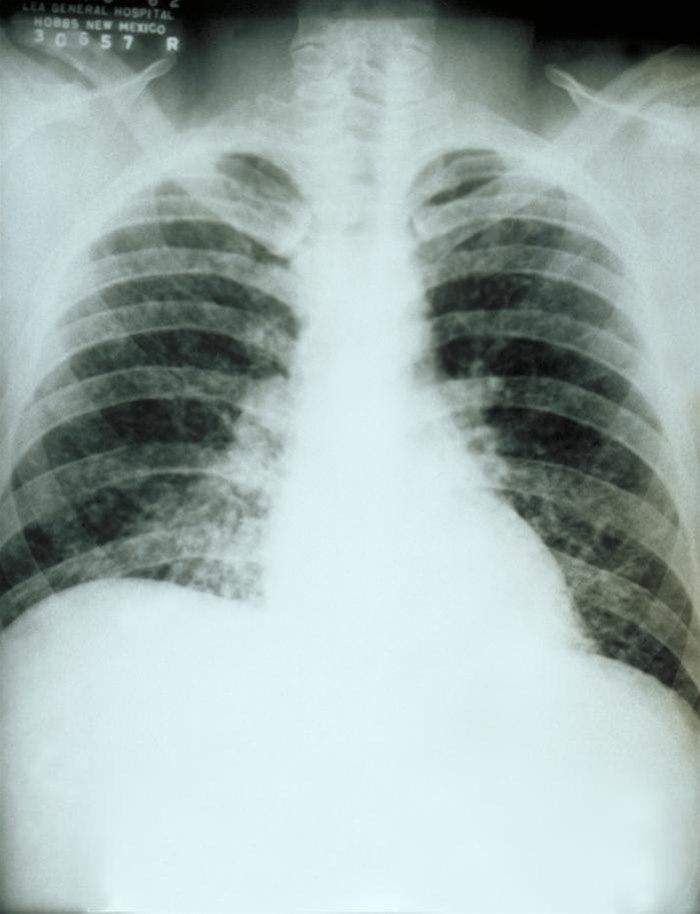

LungehistoplasmoseOpplysninger om reisemål, grottebesøk og luftveissymptomer kan gi mistanke om diagnosen. Blodprøver på antistoffer, eventuelt dyrkningsprøver fra luftveiene, kan bekrefte diagnosen. Røntgen-bilder av lungene kan vise typiske funn.